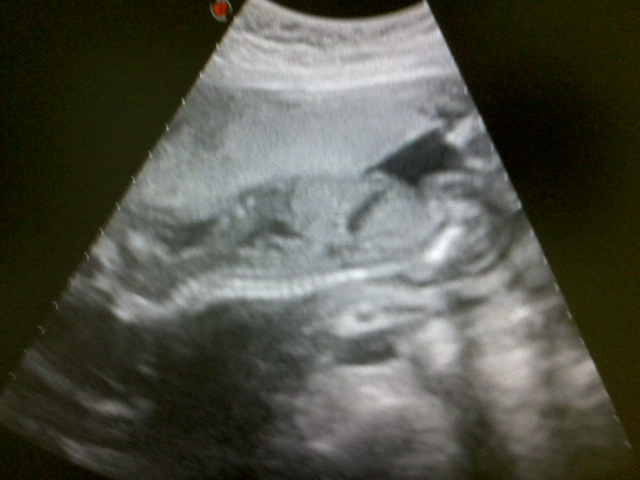

Сегодня ходила на УЗИ и оказалось,что в домике живёт у нас снова мальчуган.Видимо придётся в третий раз сходить в детский магазин за девочкой

Никак не пойму как малыш лежит.Лицом вниз?